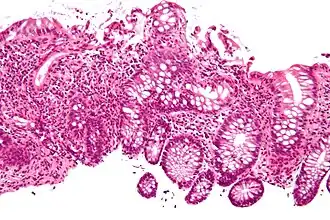

Cryptitis

In histology, cryptitis refers to inflammation of an intestinal crypt.

Cryptitis is a non-specific histopathologic finding that is seen in several conditions, e.g. inflammatory bowel disease,[1] diverticular disease,[2] radiation colitis,[3] infectious colitis.

Cryptitis. H&E stain. -